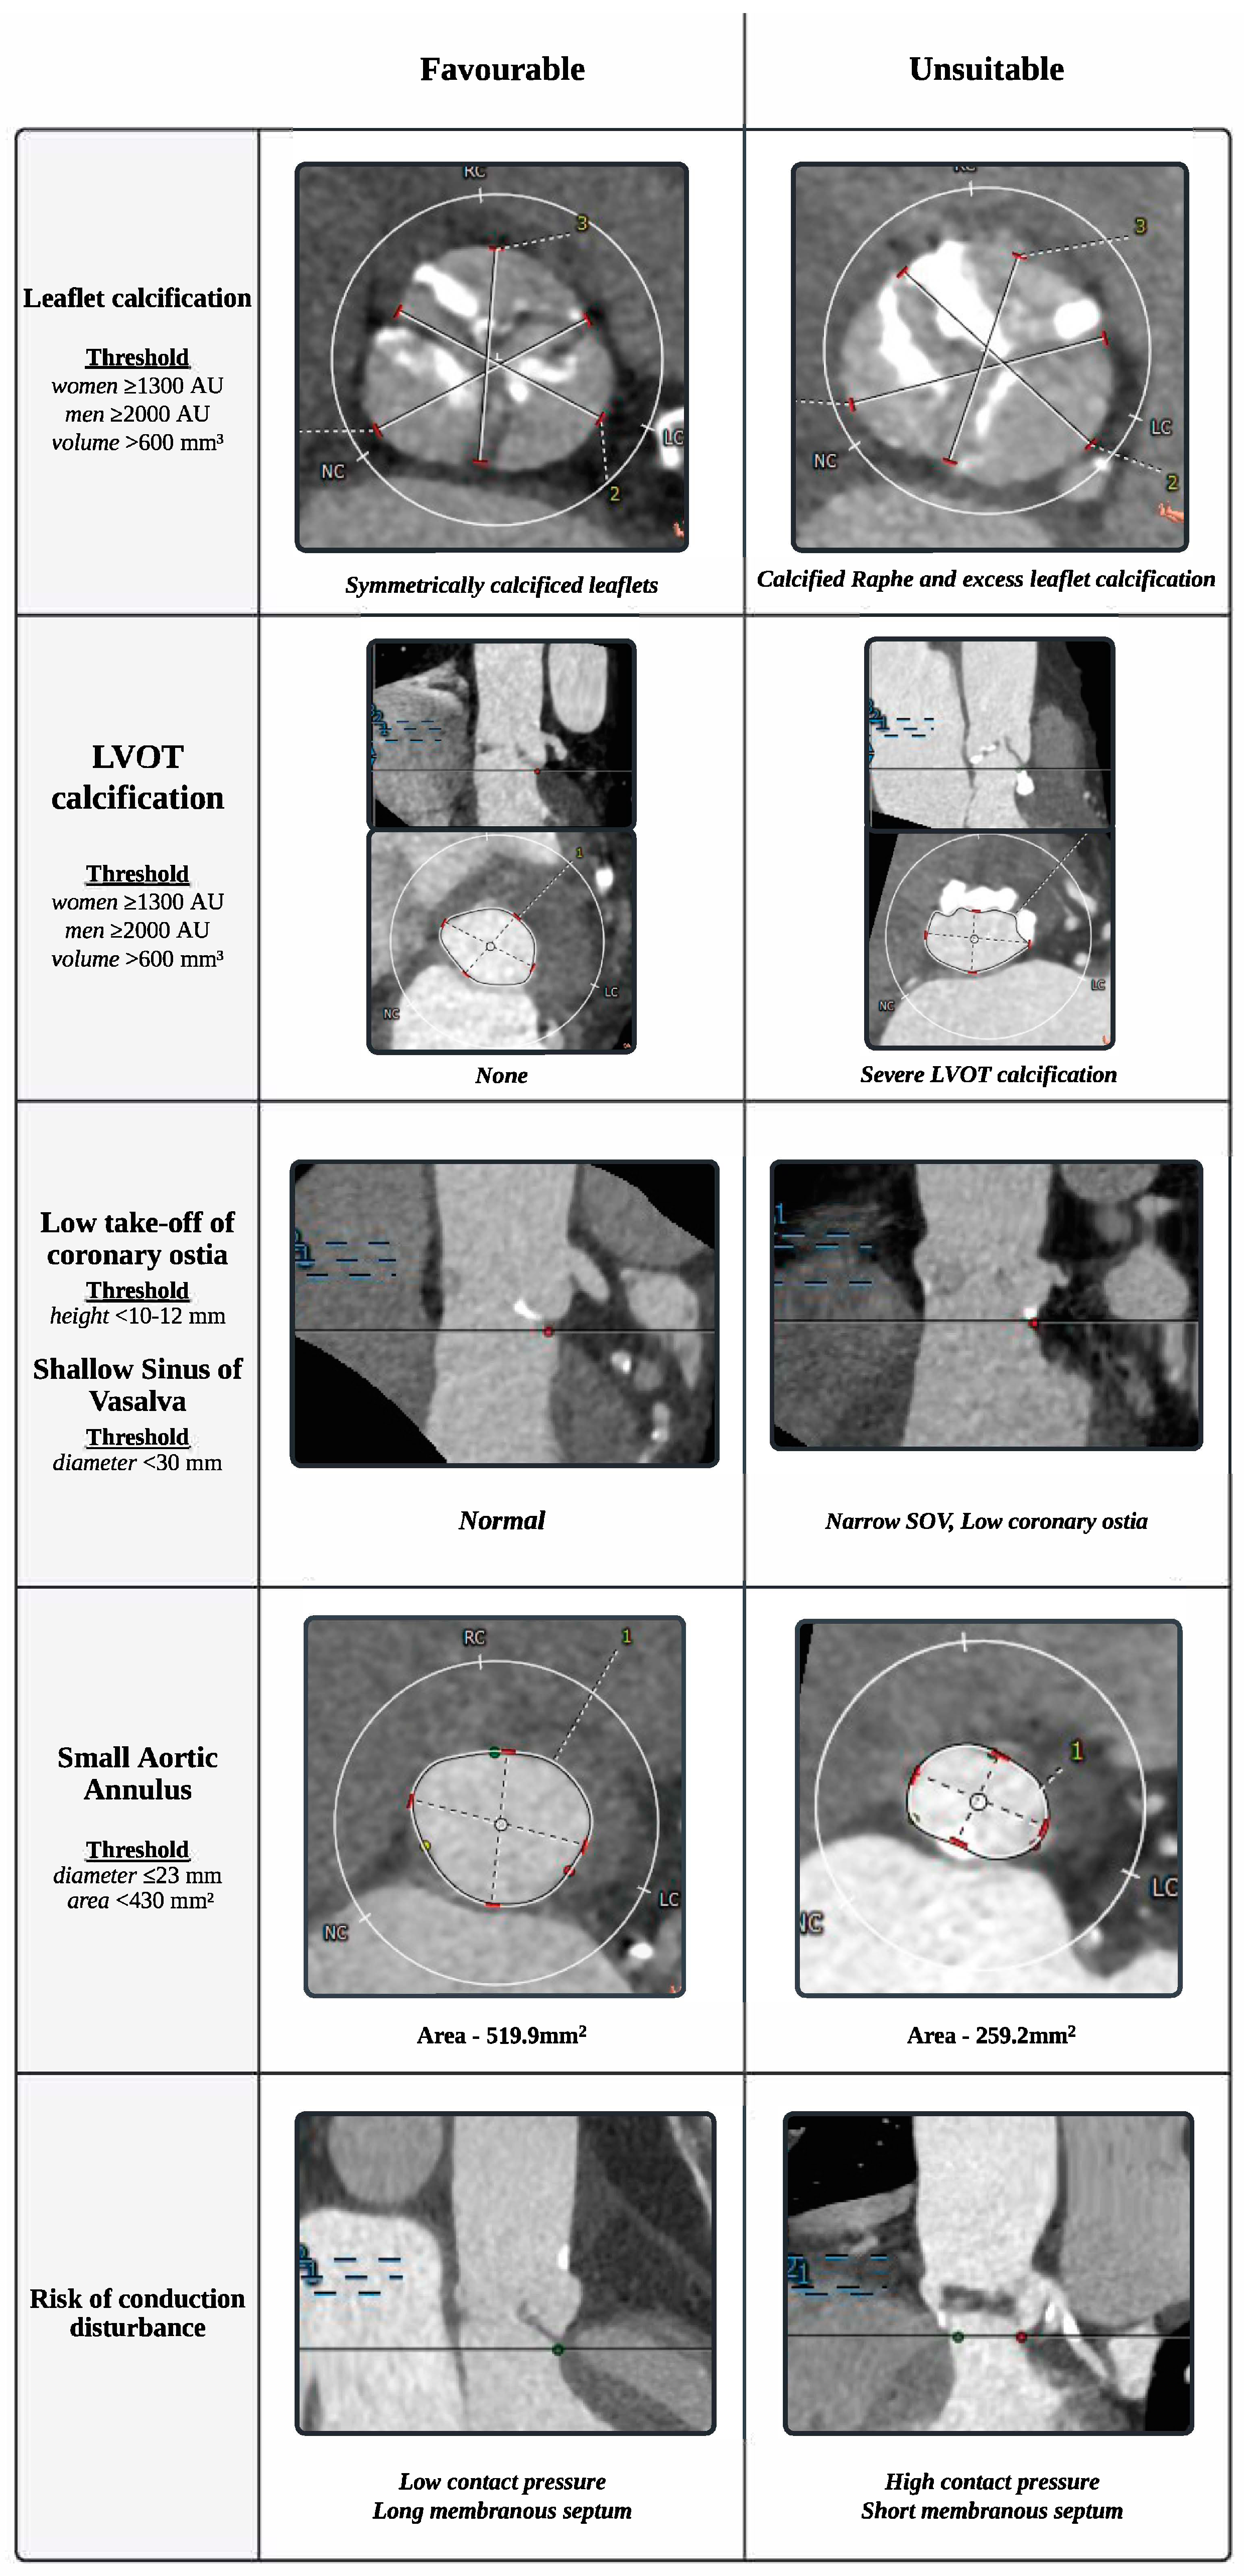

2. Complex Anatomy Unsuitable for Tavi

2.3. Annular and Left Ventricular Outflow Tract (LOVT) Calcifications

2.4. Low Take-Off of Coronary Ostia and a Shallow Sinus of Valsalva

2.5. Small Aortic Annulus